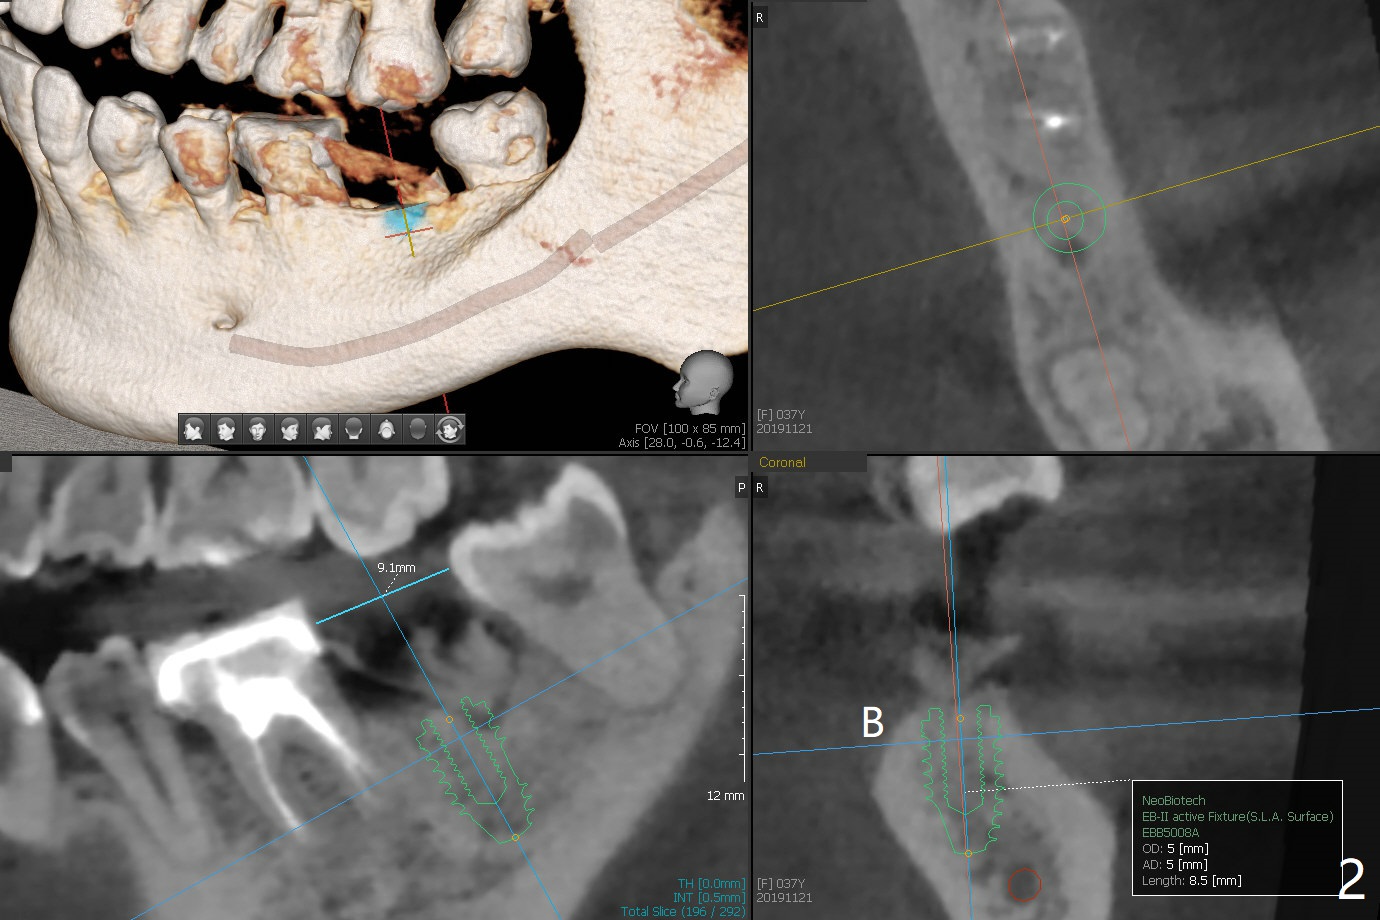

A 37-year-old woman, dental phobic, agrees to have implant at #18 (Fig.1). Since the mesiodistal and buccolingual widths of the edentulous area are moderate (Fig.2), a 5x8.5 mm implant seems to be big; a 4.5 mm one is better. The buccal and lingual bone resorption appears to be severe at #6 of the same patient postop.